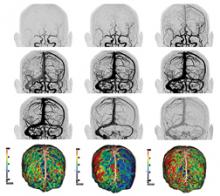

Angiographic imaging system vendors have developed several new technologies to address emerging cath lab trends, including the need to reduce radiation dose, improve image quality and enable advanced procedural image guidance. All three of these points have become increasingly important as more complex procedures are attempted in interventional labs and hybrid ORs. These procedures include embolic coiling, neuro-interventions, thrombectomy, aortic repair, transcatheter aortic valve replacement (TAVR), mitral clip valve repairs, left atrial appendage (LAA) occlusions, atrial and ventricular septal defect closures, and new interventions for both electrophysiology (EP) and heart failure.